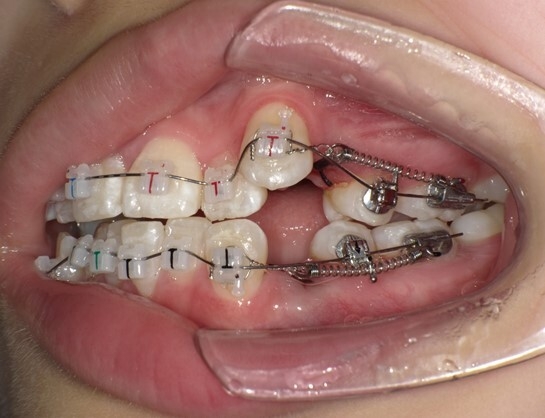

患者は13歳8か月の女子。主訴は左上に八重歯があること。上顎両側、下顎左側第一小臼歯を同時抜歯し、JET systemで治療を行ったところ動的治療期間は7か月であった。前歯部のトルクコントロール、上下顎正中の一致、咬合関係の改善が行われた。抜歯により誘発されたRAPを利用したJET systemでの治療は、治療期間の短縮に寄与し、患者QOLを向上させることが示唆された。

この症例のように身体の成長途上にある中高生であれば、治療を6~9か月で終えることができる可能性があります。歯列矯正治療では、平均して治療に2~3年にわたることが一般的ですが、JET systemによる最も顕著な患者さんのメリットは治療期間の短縮です。長期にわたる治療のストレスや生活の制約、ブラケットによる見た目への懸念、矯正装置の使用にともなう不快感を短期間で終えることができます。また、JET system専用に開発したブラケットを使用することで、これまでよりも弱い矯正力で治療を行うため痛みが少なくなります。JET systemは、患者さんのモチベーションを維持し、治療効果や患者さんの満足度向上につなげることが期待できます。